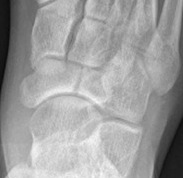

Imaging

Acute, minimally displaced navicular fracture

Acute displaced navicular fracture